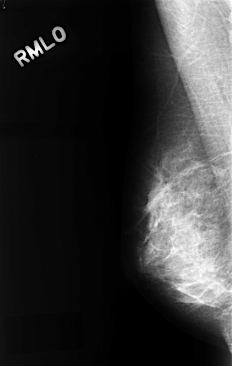

ics_version 1.0 filename C-0323-1 DATE_OF_STUDY 1 2 1995 PATIENT_AGE 48 FILM FILM_TYPE REGULAR DENSITY 4 DATE_DIGITIZED 8 10 1998 DIGITIZER LUMISYS LASER SEQUENCE LEFT_CC LINES 4528 PIXELS_PER_LINE 2984 BITS_PER_PIXEL 12 RESOLUTION 50 OVERLAY LEFT_MLO LINES 4352 PIXELS_PER_LINE 2824 BITS_PER_PIXEL 12 RESOLUTION 50 OVERLAY RIGHT_CC LINES 4448 PIXELS_PER_LINE 2848 BITS_PER_PIXEL 12 RESOLUTION 50 NON_OVERLAY RIGHT_MLO LINES 4384 PIXELS_PER_LINE 2784 BITS_PER_PIXEL 12 RESOLUTION 50 NON_OVERLAY |